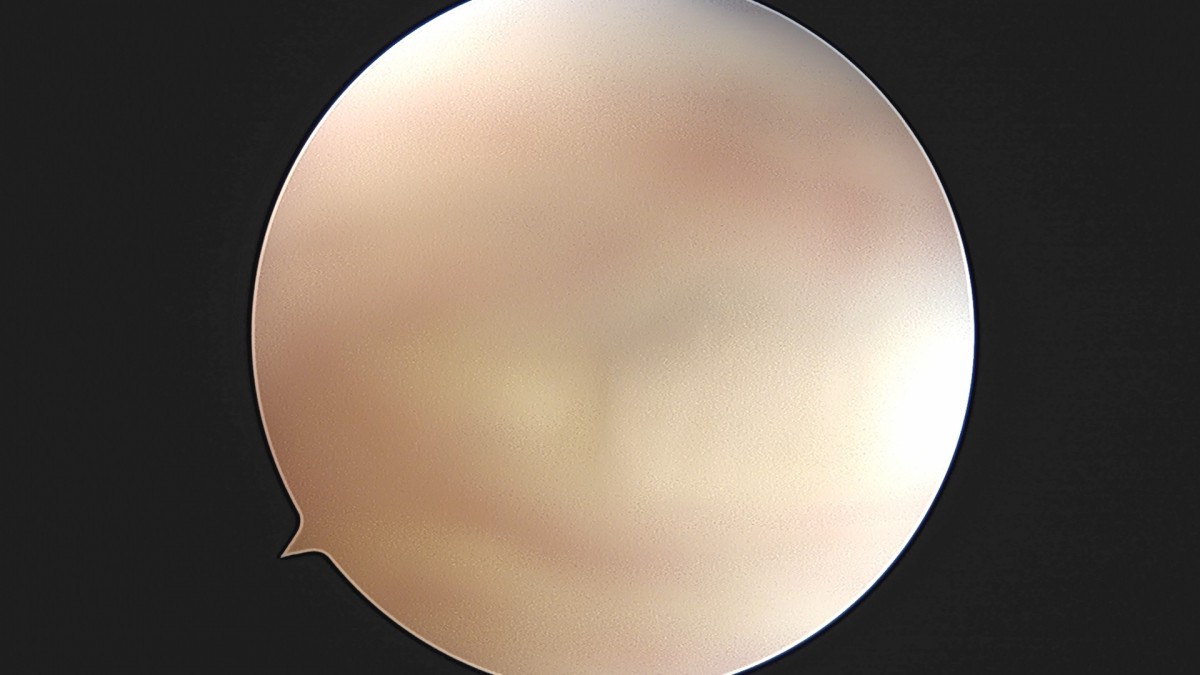

이재상원장님 무릎 반월상 연골판 절제술 최용O 환자

dae765e4d9ac96aee867c9d6292d8784_1758005819_409.jpg